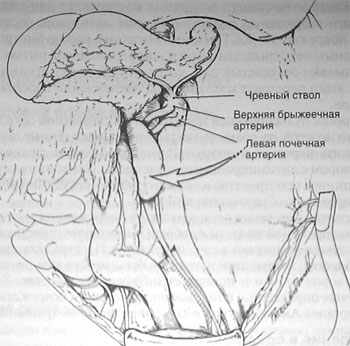

Раздел: Образы вокруг